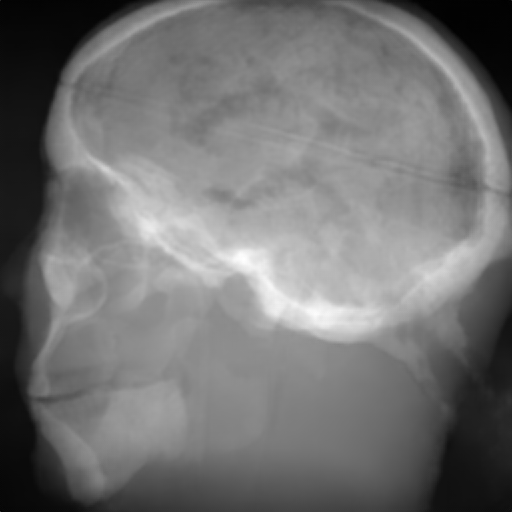

(a) Input: MR proj.

(b) Output: U-net p-loss.

(c) Output: ResNet p-loss.

(d) Output: CRN p-loss.

(e) Reference: X-ray proj.

Figure 2: Results of the projection synthesis. Top row: Results generated with the perceptual-loss function. Bottom row: Results generated with the 1subscript1\ell_{1}-loss function.

The quantitative and qualitative results of the proposed experiments are presented in Table I and Figure 2. By examining these it can be observed that the differences in the calculated MSE of all network architectures and incorporated loss functions are only small. The best results in terms of pixel-wise deviation could be achieved with the ResNet architecture combined with the 1subscript1\ell_{1}-loss function. This network achieves a deviation from the reference of only 0.058, i.e., 2.4 percent. Also the results of the U-net and CRN networks are still good with deviations of 2.6 and 2.9 percent. Similarly small variation can be observed in the structured similarity measure. The ResNet and CRN exhibit approximately equal quality with SSIM measures of 0.938 and 0.920 for the 1subscript1\ell_{1}-loss and 0.924 and 0.931 for the perceptual-loss, respectively. The results generated with the U-net are slightly worse. The highest peak signal-to-noise ratio is achieved by the ResNet (1subscript1\ell_{1}-loss), followed by the U-net (1subscript1\ell_{1}-loss) and CRN (p-loss). It is noteworthy that the ResNet and U-net both achieve the highest results in all error metrics using the 1subscript1\ell_{1}-loss while the opposite is the case for the CRN which works best with the perceptual-loss function.

Overall, the perceptual-loss achieves competitive and in some cases even better results than the 1subscript1\ell_{1}-loss when comparing the pixel-wise error metrics. For example, the cascaded refinement network’s MSE is 0.013 smaller for the perceptual- than for the 1subscript1\ell_{1}-loss. This might be suspicious at first sight, considering that the 1subscript1\ell_{1}-loss purely optimizes for this pixel-wise error in the training process while the perceptual-loss compares the raw feature activations of the evaluation network. Contrarily, this behavior cannot be observed for the U-net and ResNet. The results produced with the 1subscript1\ell_{1}-loss achieve higher values for all error measures for these networks. An explanation for this obervation is that the intensity values of the input image still cause an impact on the respective layers output in the evaluation network when computing the perceptual-loss. Consequently, these differences also transition to the computed loss value for all feature layers. Even though the perceptual-loss incorporates the raw intensity values, it is not guaranteed that the scaling of these is conserved in this process. By this, the relative changes can be similar, whereas the absolute range of values changes and, correspondingly, also the pixel-wise error metrics.

Another observation is that the perceptual-loss is able to conserve high-frequency details in the image. The fine line in the projection images that forms a circle around the cranium is visible in the input (Figures 2a & 2f), as well as in the label images (Figures 2e & 2j), and also in the images generated with the perceptual-loss function (Figures 2b2c, and 2d). In contrast, all generators ”loose” this line when the 11\ell 1-loss is applied (Figures 2g2h, and 2i). This effect is also qualitatively observable in other parts of the images. Despite achieving equal or better results regarding the error metrics, the generally less sharp look of the results generated with the 11\ell 1-loss function is apparent. This behavior is in accordance with previous observations that concluded that an perceptual-loss leads to sharper images than a comparable 11\ell 1-loss [19]. Considering the common applications of X-ray Fluoroscopy, e.g., interventional guidance for stents and similar devices, high spatial resolution is a key requirement. Utilizing a loss function that is able to preserve high-frequency details in the images is desirable to this end. The perceptual-loss appears to be suited for this task as presented in our evaluation.